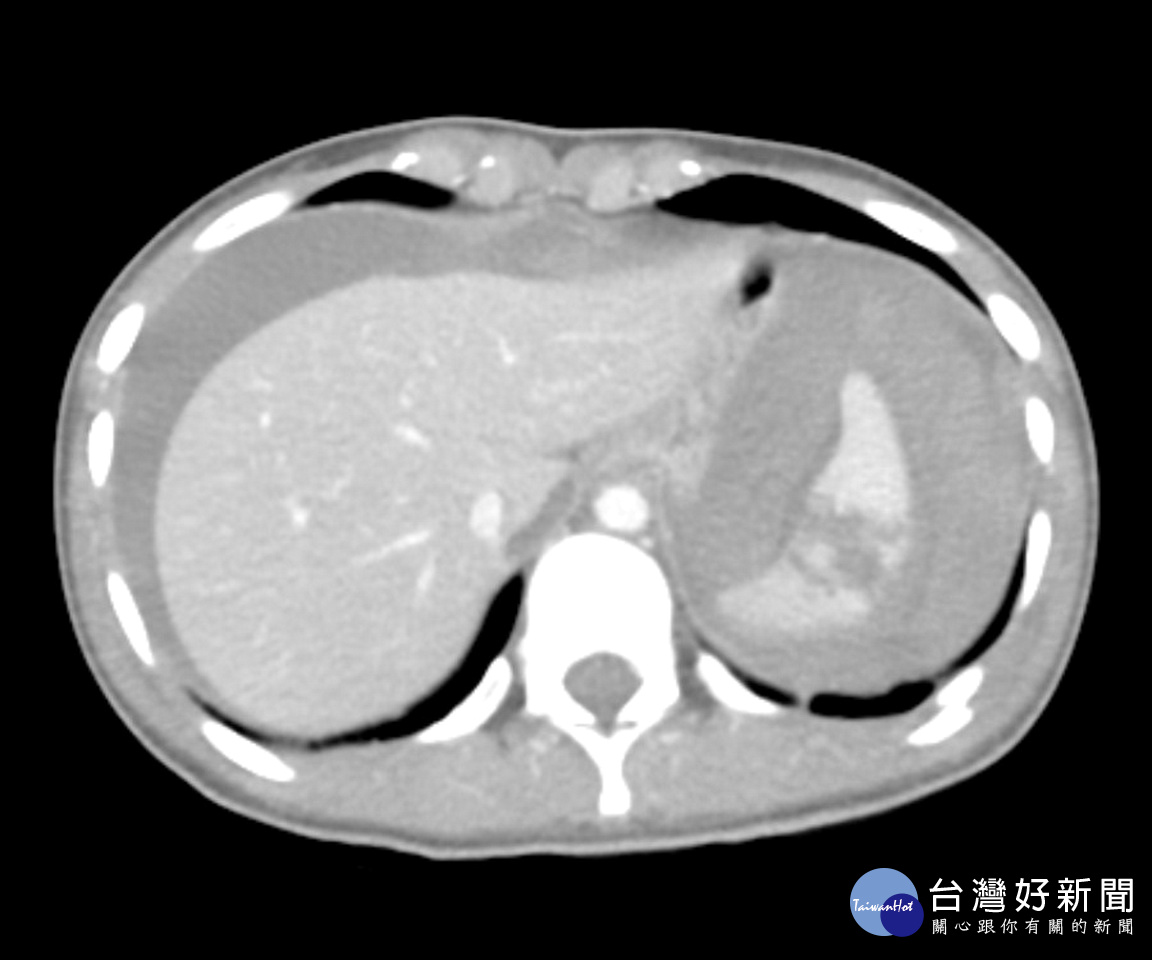

一位20歲就讀護理學系的吳姓女大生,日前於南投縣集集鎮上不幸發生車禍意外,緊急被送往鄰近的竹山秀傳醫院進行救治,急診醫師發現女大生臉色漸趨蒼白且有休克徵象,經超音波檢查與電腦斷層掃描診斷為脾臟破裂合併大量腹內出血(附圖),院方立即啟動重大外傷病人救護機制並安排緊急手術進行止血,術後女大生生命徵象漸趨穩定轉至加護病房接受後續治療,近日已康復出院休養。

外科部主治醫師蘇啟成表示,脾臟破裂出血是一種嚴重的外傷急症,出血速度極快,病人常會迅速休克甚至死亡,女大生體重僅約40公斤,術中發現內出血已逾3000毫升,幾乎是瀕死狀態,開刀是在與時間賽跑,所幸最後終於成功搶回一條年輕生命。蘇醫師也呼籲民眾在車禍當下切莫自行評估身體狀況,宜盡速就醫以避免延誤搶救時機。